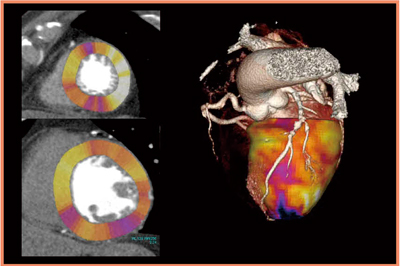

・症例6:70歳代,男性。糖尿病のフォロー中に,心エコーで左室躯出率(EF)の低下が指摘された。

冠動脈CTAで,LAD領域に境界域の狭窄病変が認められた。負荷心筋パーフュージョンCTでは,LAD領域に若干の低下域があるものの,重度ではないことがわかった(図8)。この患者は心筋シンチグラフィでも同様の所見であり,現在フォロー中である。

図8 症例6:LAD狭窄症例の心筋パーフュージョンCT